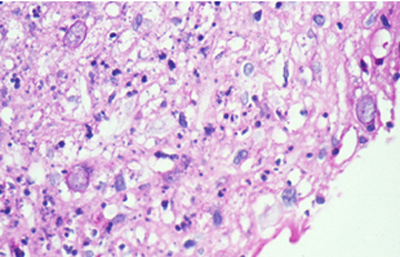

Tanto las Acanthamoebas vivas como sus productos de degradación son marcadamente antigénicos. En la respuesta celular a la infección por Acanthamoeba, los macrófagos las fagocitan (Fig 19) y los neutrófilos las destruyen vía secreción de mieloperoxidasas. (Figura 20) (Para no frenar la respuesta celular, preferimos no usar corticoides en el tratamiento de la infección activa). (El uso crónico de corticoides, en casos con superficie corneal alterada, es un factor primario en el desarrollo de una queratopatía cristalina infecciosa). La respuesta celular tiene como consecuencia, cuando la invasión por Acanthamoebas es estromal, que la abscesificación del estroma continuará aumentando a pesar del tratamiento, siendo su resolución lenta. (Figura 21, 22, 23, 24, 25, 26) (Figura, 27, 28, 29 y 30)

Fig. 19 Acanthamoeba fagocitada por macrófago. Giemsa, Original x160

Fig. 20 Trofozoito rodeado por polimorfonucleares. Giemsa, Original x160